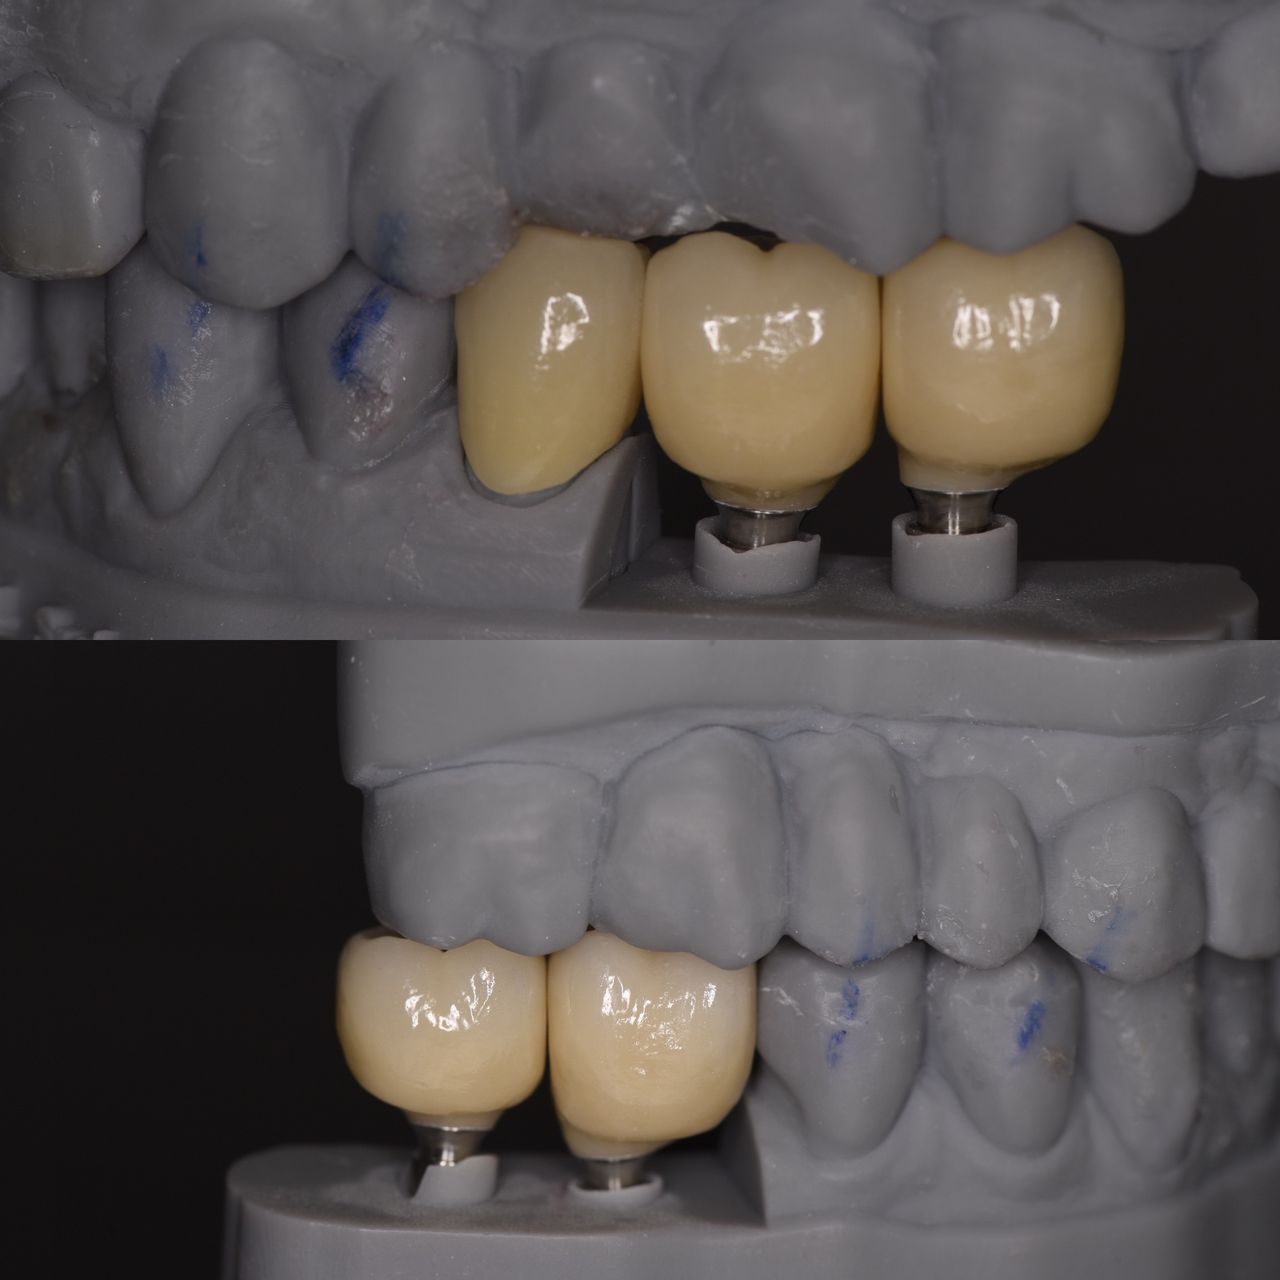

- protetyka (korony ceramiczne (cerkon, E-max), licówki, mosty, protezy ruchome, korony na teleskopach, inlay, onlay, overlay, endkorony);

- implantologia,